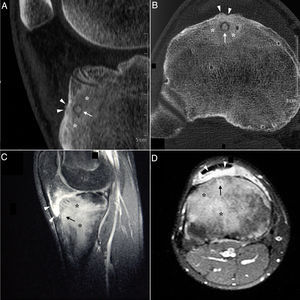

Sagittal (A) and axial (B) computed tomography images of right knee showing an osteolytic lesion in the subendosteal region of the anterior tibial tuberosity, with a “nidus” formed by ossified matrix, compatible with osteoid osteoma (arrow), encircled by extensive sclerosis of the surrounding medullary bone (asterisks) and a solid periosteal reaction in the adjacent cortical bone (arrowheads). Post-gadolinium sagittal (C) and axial (D) T1-weighted spectral presaturation with inversion recovery (STIR) magnetic resonance images revealed perilesional contrast uptake in the form of a ring (arrow), and in surrounding bone edema (asterisks) and Hoffa fat pad (arrowheads).